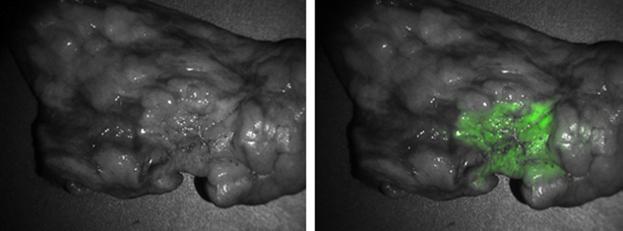

Upon opening the chest cavity, the primary lesion was located using traditional methods of visual inspection and manual palpation. The cancer was imaged and photo-documented with a specialized imaging system [Artemis Fluorescence Imaging System (Quest Medical Imaging) and the FloCam system (developed in their laboratory)].

Of the remaining 43 tumors, 39 appeared fluorescent after the overlying tissue was opened and the tumor exposed. The fluorescence was uniform across the tumor's surface, and the demarcation between tumor and normal surrounding tissue was clearly visible. On average, the optical imaging was quick, ranging from five to 15 minutes.